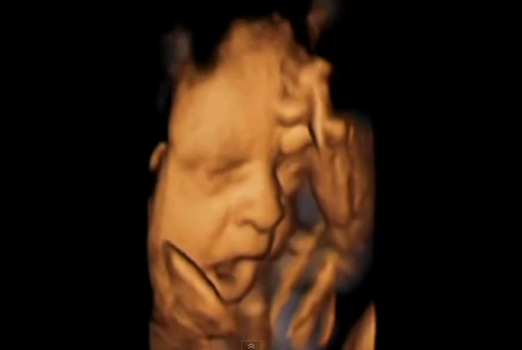

The Most Amazing Piece Of Research: 4D Scan Shows Babies Yawning In The Womb

This remarkable video shows a baby yawning in the womb.

It is one of dozens produced by Durham University researchers who were fascinated by whether foetuses yawn and, if so, why.

4D ultrasound scans are the latest in gynaecology technology. Rather than the grainy ‘flat’ images produced by the 2D scanners usually used, a 4D machine stitches together pictures taken from a variety of angles to create clear three-dimensional images.

These are then recorded on video, the fourth dimension. Researchers painstakingly analysed these highly detailed videos frame by frame to see how the foetuses moved their mouths.

On some occasions, a baby would slowly open their mouth, before quickly snapping it shut, characteristics of a yawn.